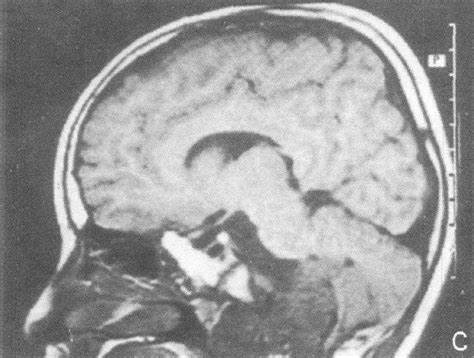

脊索瘤起源于残存脊索细胞,是一种少见的原发骨肿瘤。当脊索的胚胎残留物在出生后未退化,可能逐渐演变成脊索瘤。该病好发于50~60岁,男女比例约为2:1,且几乎只发生在中轴骨,尤其是骶尾部(约50%)、颅底(约35%)...【全文】